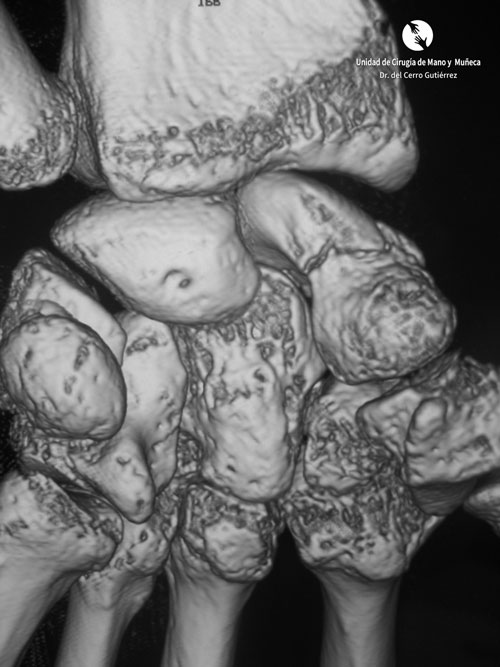

Fractura del escafoides. Reconstruccion con TAC

Fractura del escafoides. Reconstrucción con TAC